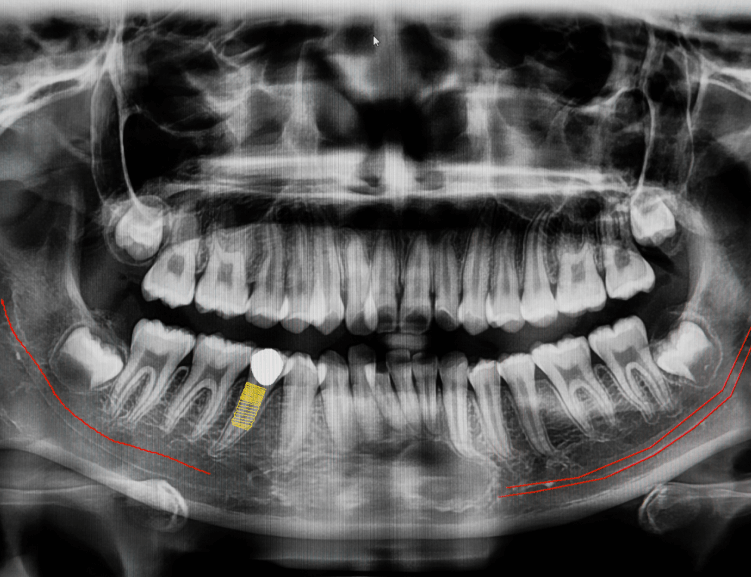

Jaw surgery, also known as orthognathic surgery, is a corrective procedure to address irregularities of the jaw bones and improve their alignment. This treatment not only enhances function but also improves facial appearance.

At Diva Dental Clinic, we combine expertise and state-of-the-art technology to deliver outstanding results tailored to your needs.